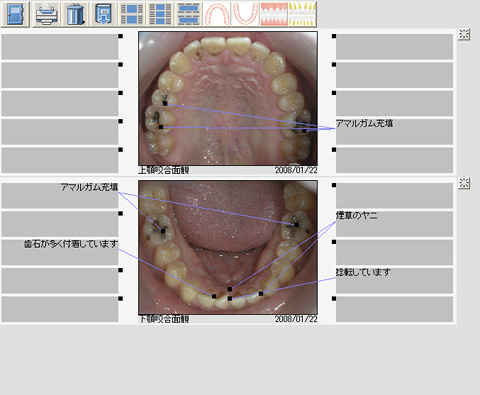

機能紹介/お口の状態を詳細に解説

画像の説明したい箇所に簡単に引込み線とコメントを添えられますのでより明確に説明することができます。

お口の状態を詳細に解説